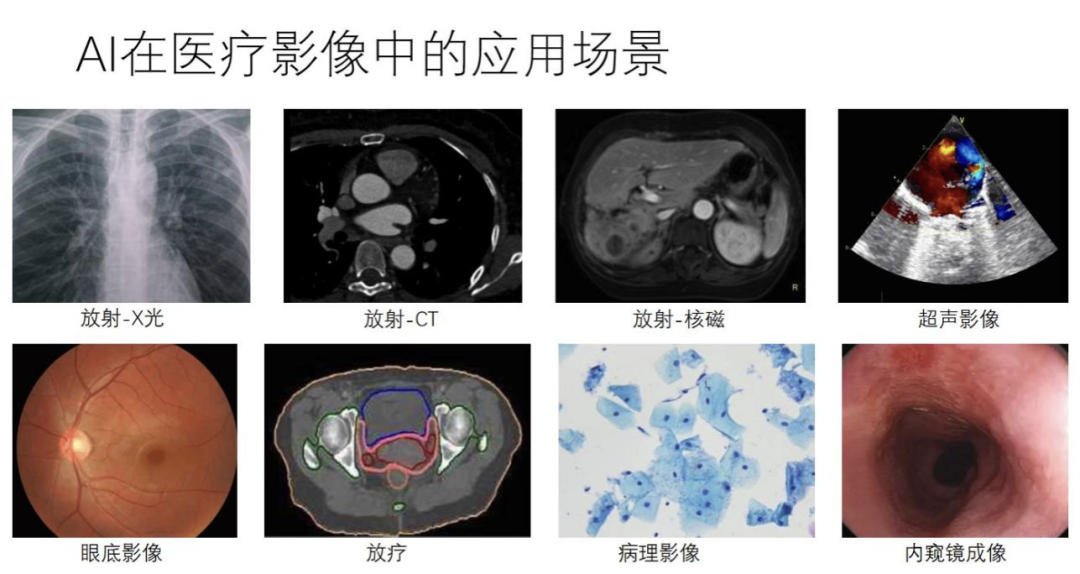

医疗影像领域第一个难点在于影像任务比较丰富多样,比较碎片化。因为每个影像任务至少会受到三个主要因素的影响,第一是如何成像,第二是照哪个人体部位,第三是看哪种病。即使是一样的成像方式(比如都是 X 光或者都是 CT),如果人体部位不一样、病不一样,所做的影像分析任务也不一样。

下面我从产品本身如何去迭代和演化的角度做一个简要的介绍。从 2015 年开始,产品从复杂程度、算法和产品设计的过程来看,大概经历了四个阶段,我们称之为 1.0-4.0,从最初 2015 年的单任务单环节,过渡到多任务全流程,再过渡到多模态多场景,到现在的跨模态复合流程。从仅限影像科,到现在进入临床手术,经历了比较大的变化。